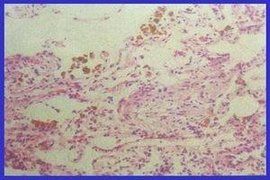

3、痰塗片普魯氏藍染色可見細胞內有藍色顆粒,為含鐵血黃素顆粒,據此可明確診斷。對嬰幼兒要抽取胃液做上述染色。